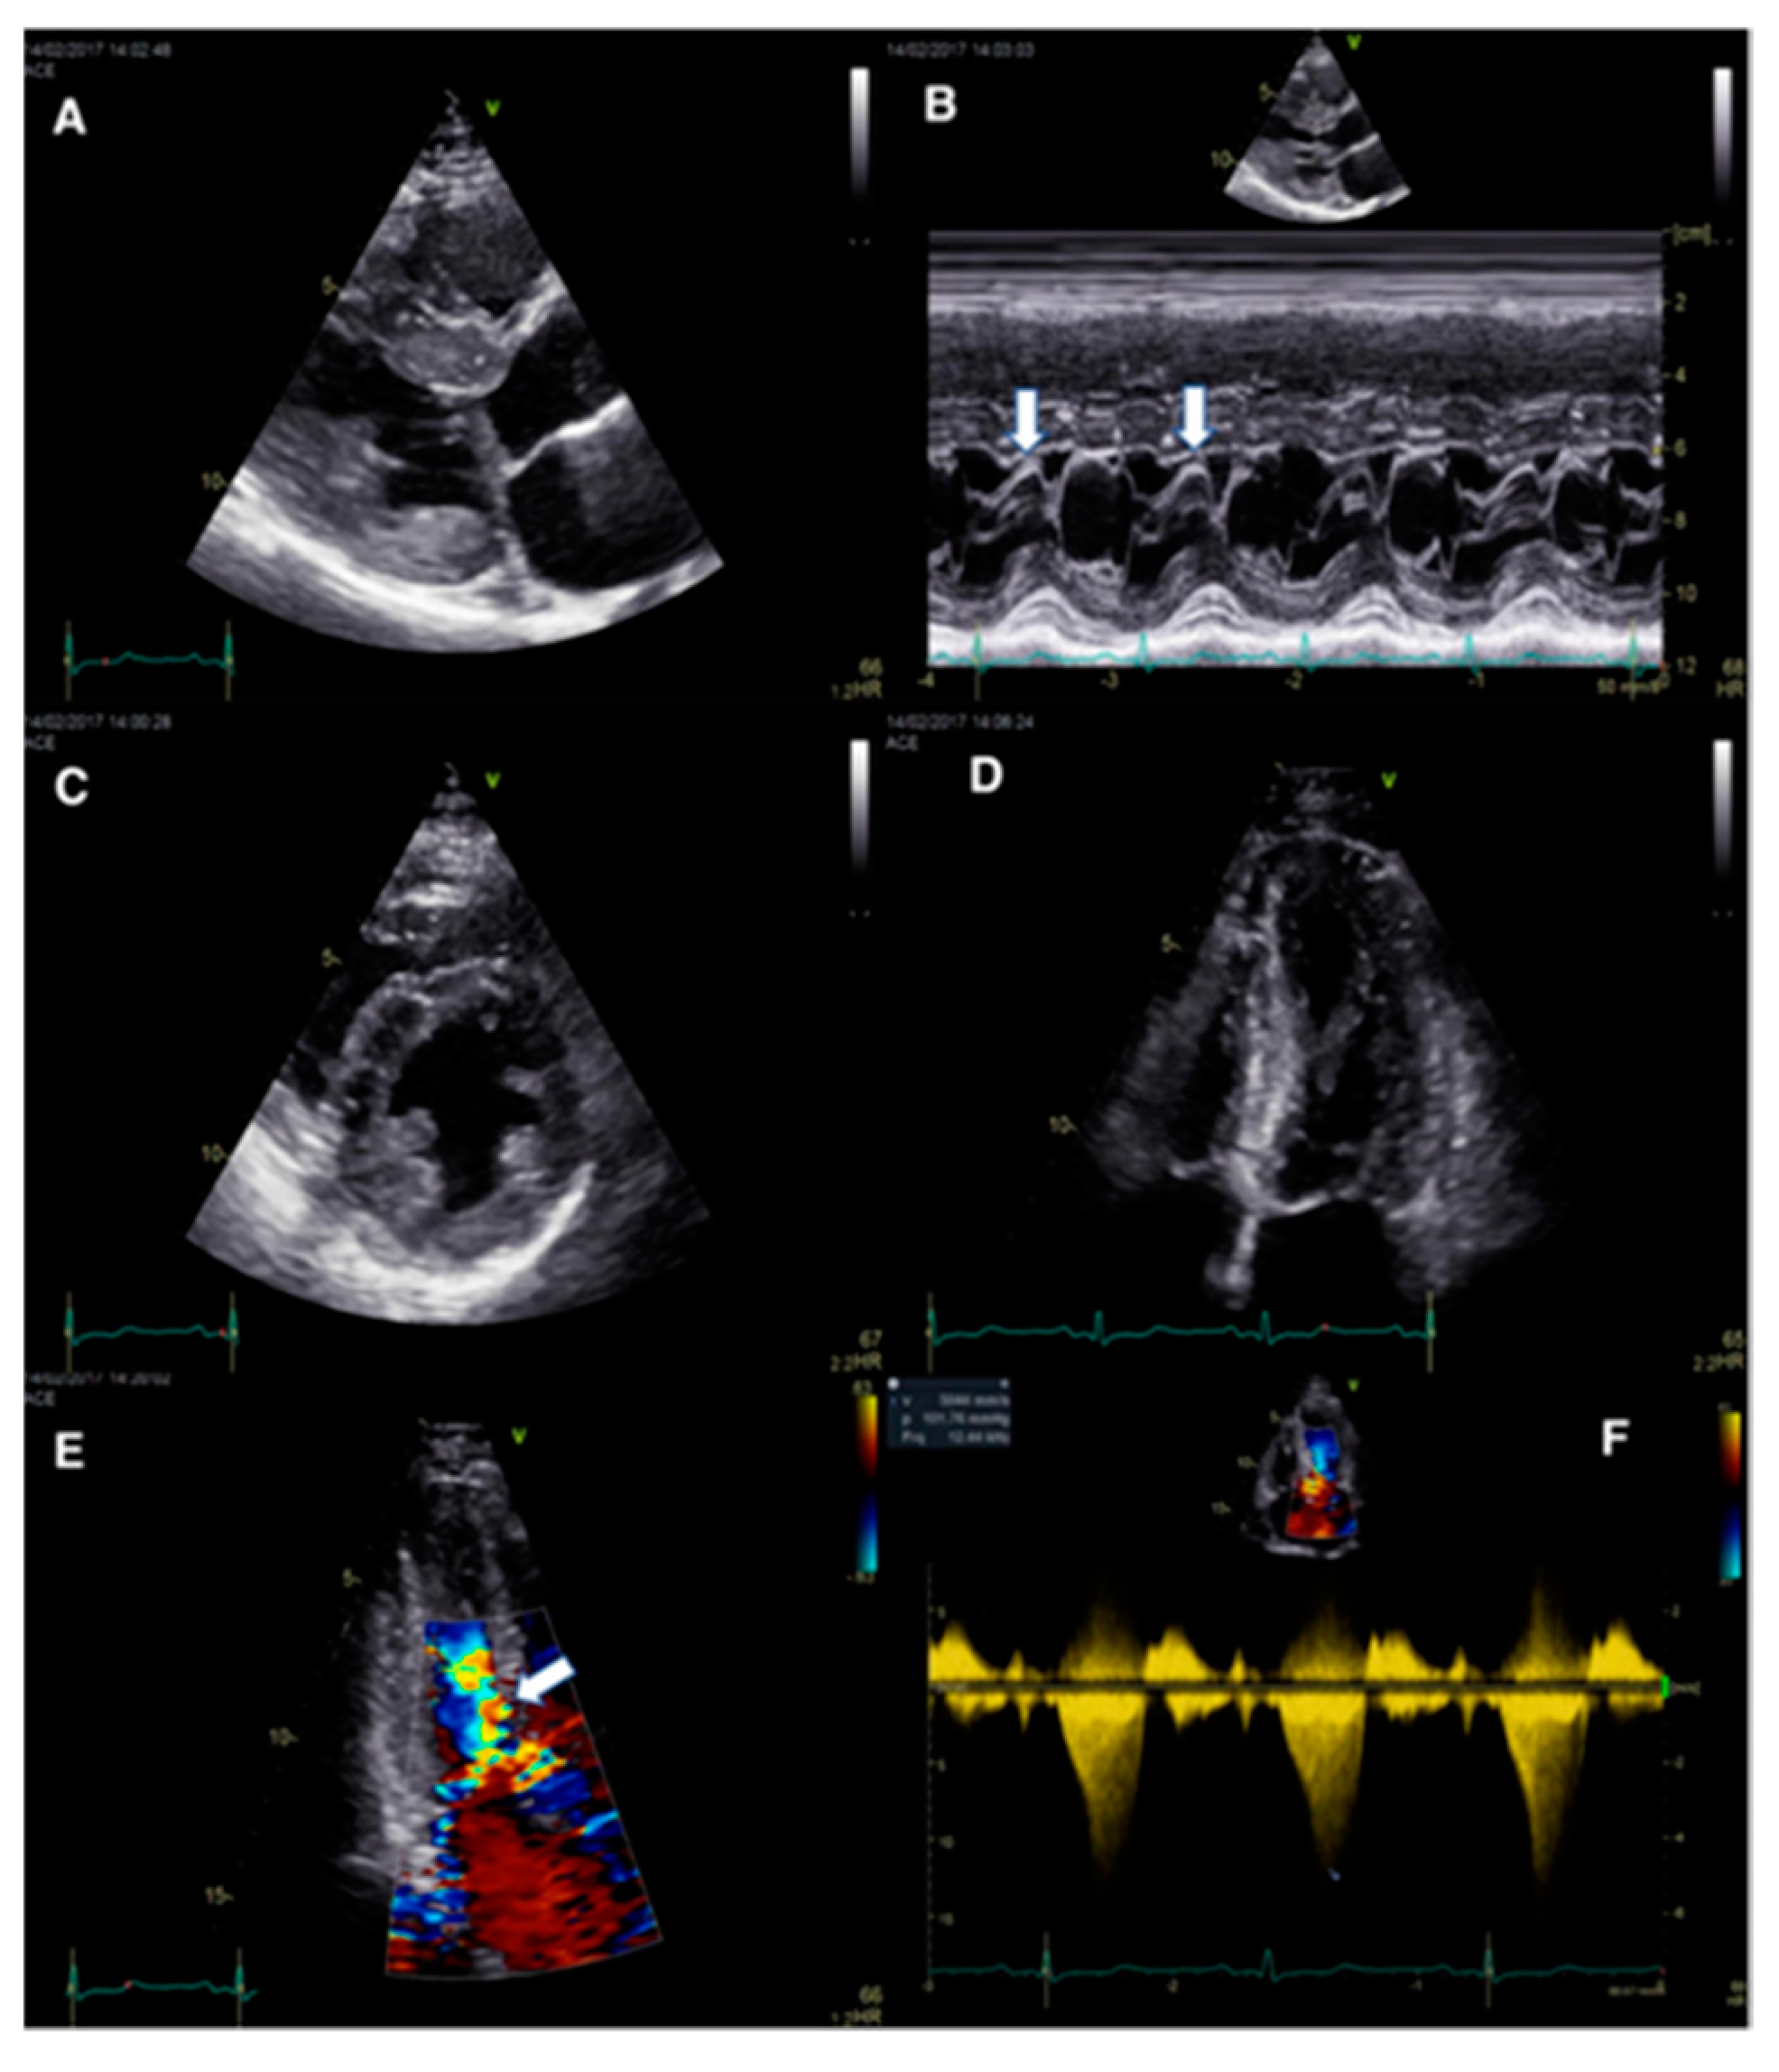

3.2. Abnormal IVS Motion

- Calle, S.; Delens, C.; Kamoen, V.; De Pooter, J.; Timmermans, F. Septal flash: At the heart of cardiac dyssynchrony. Trends Cardiovasc. Med. 2020, 30, 115–122. [Google Scholar] [CrossRef]